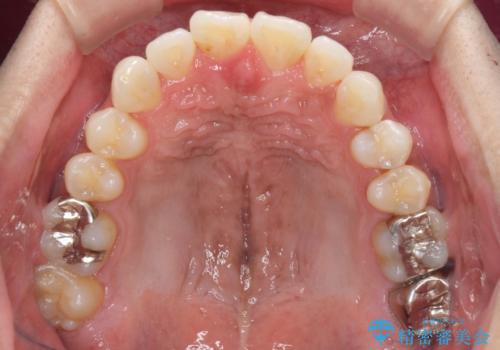

上顎の狭い歯列をインビザラインで拡大

奥歯はクロスバイトとなっているので上顎は側方拡大を行いつつ、上下全体の叢生をインビザラインにより改善することとしました。

治療途中でクリーニングやホワイトニングを行い、歯列が整うと同時に明るい口元となりました。